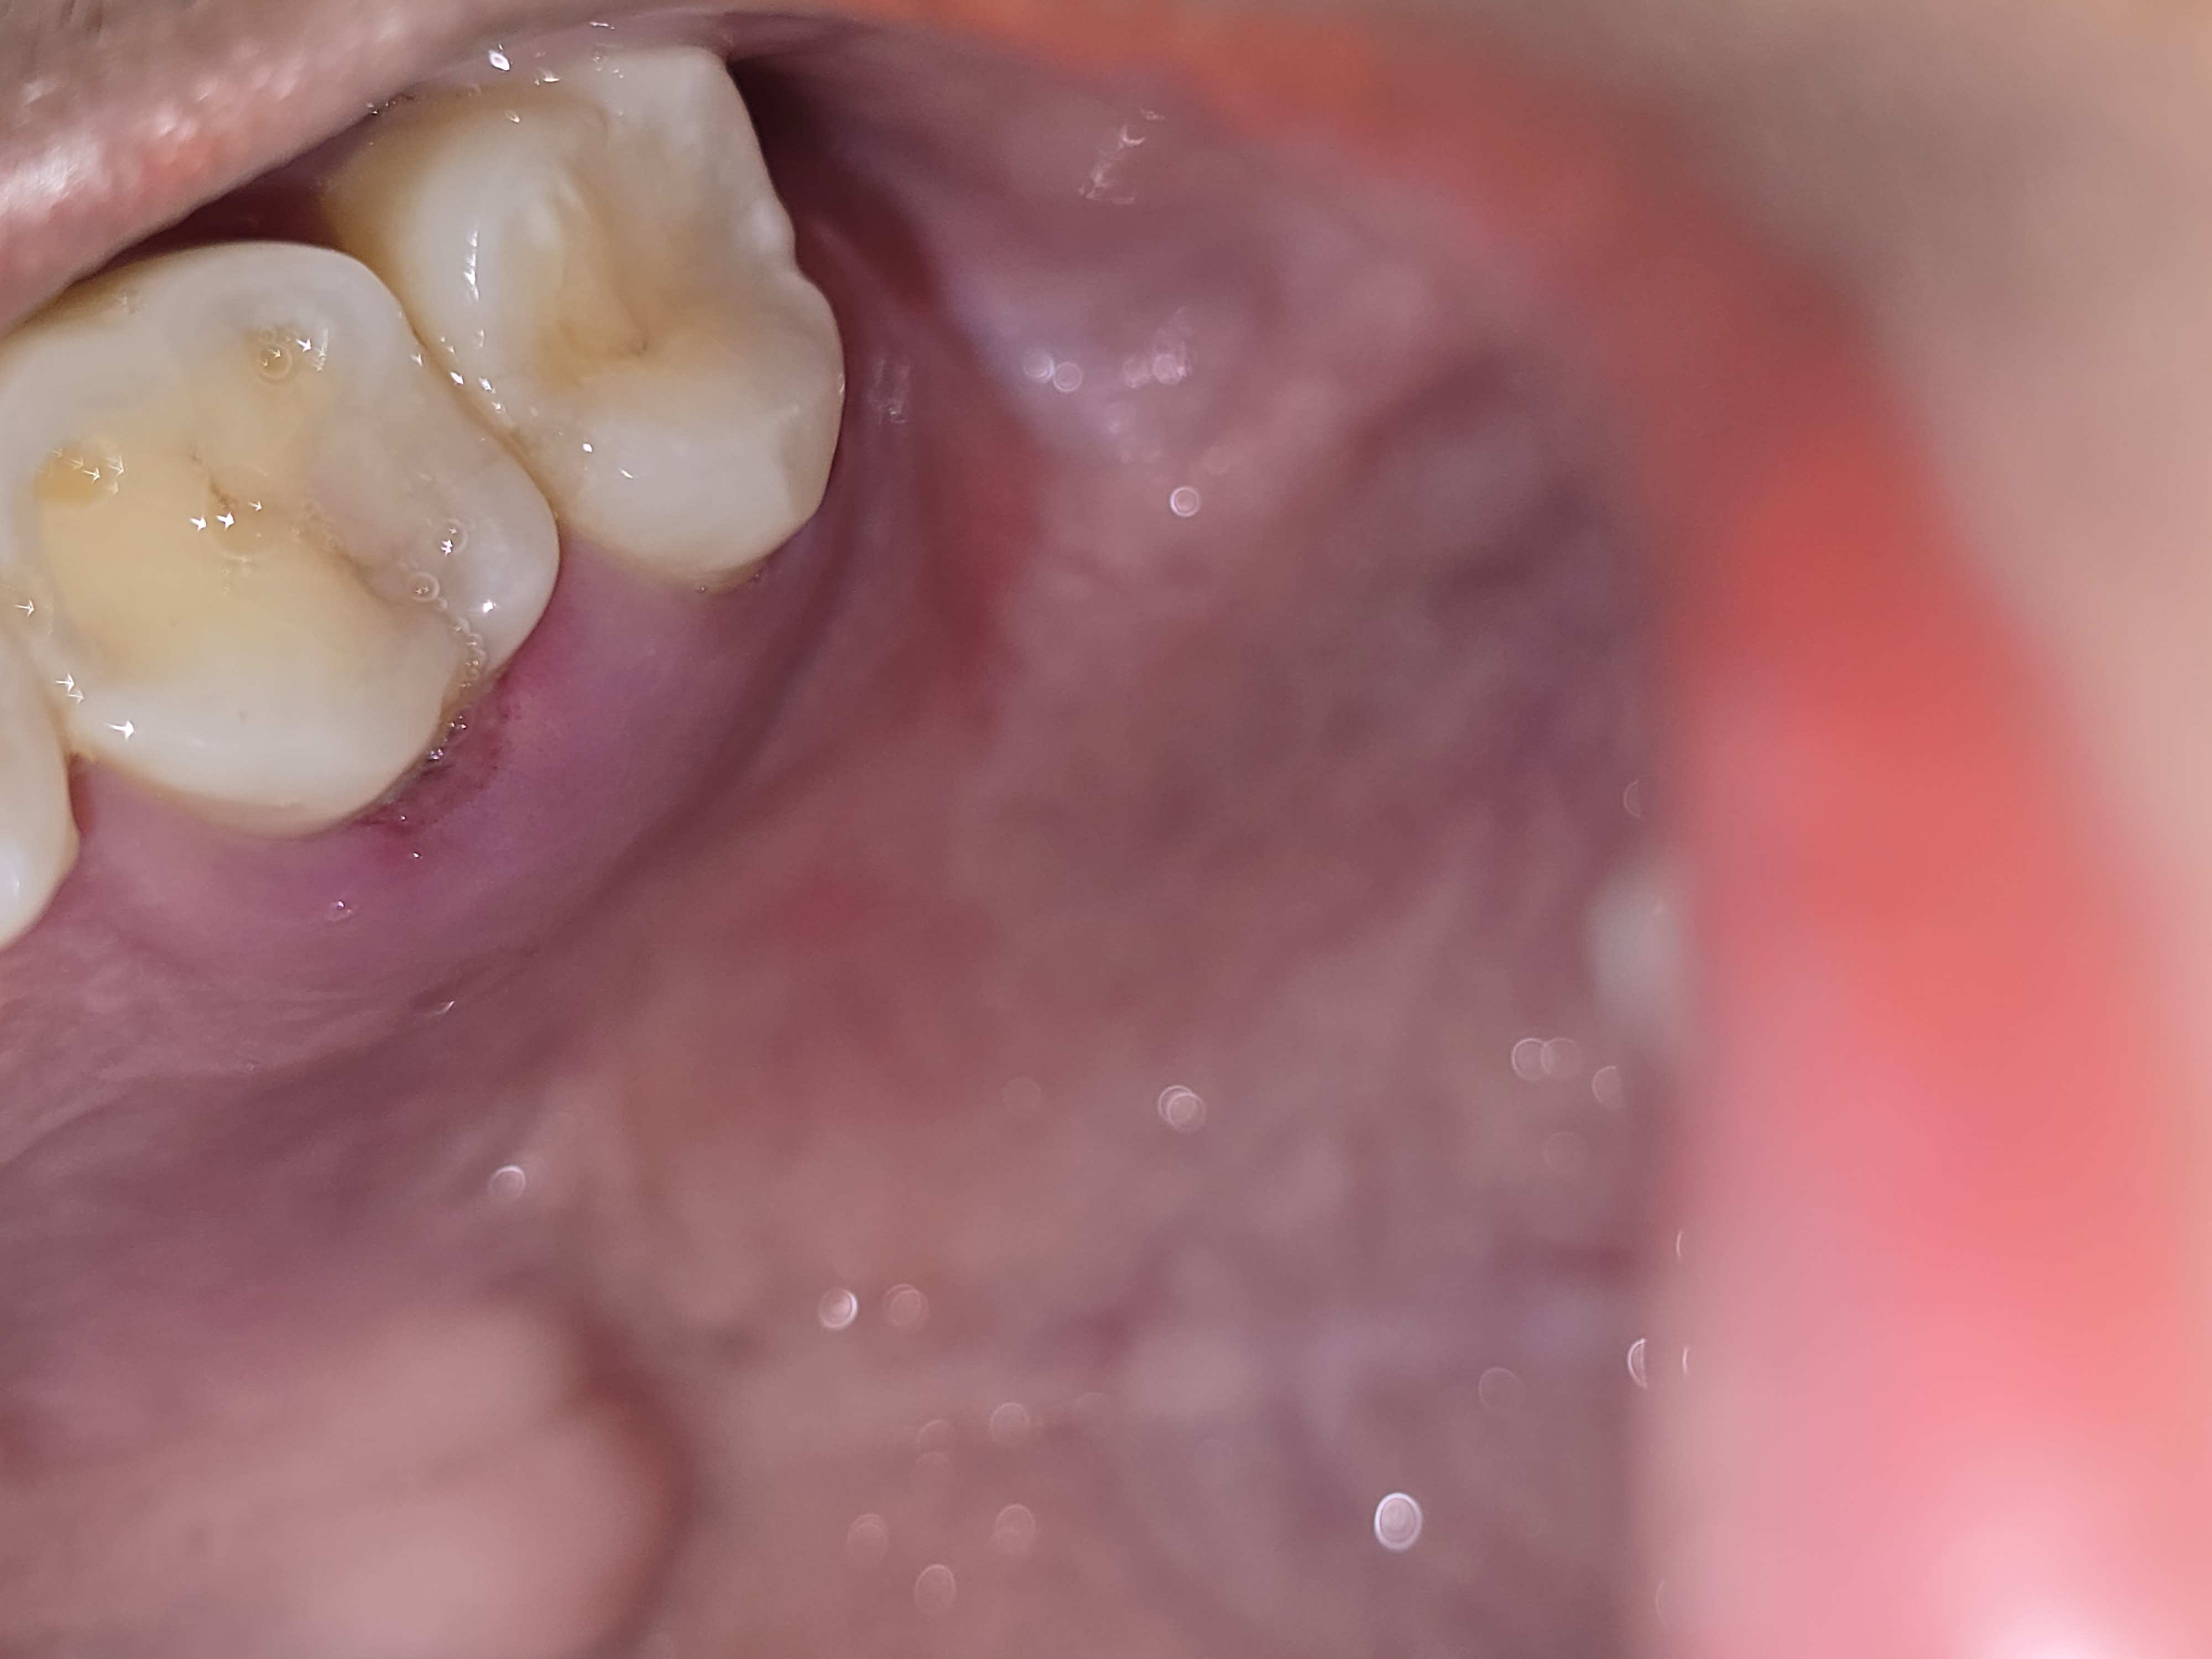

ปวดเหงือกบริเวณกราม ปวด โดนฟันแล้วเจ็บ

วันที่สองบวมน้อยลงแต่มีรอยจั้มเลือดมีหนองไหล

วันที่สามบวมอยู่และเห็นเป็นร่องแผลค่ะ